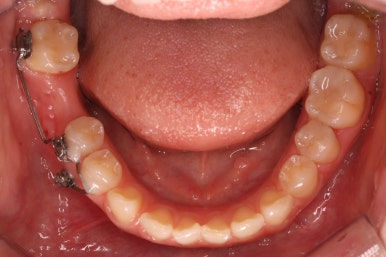

초진 때의 입안 모습입니다.

앞니는 고른 편이였으나 군데군데 틈새가 있었습니다. 약간 삐뚠 모습도 보이지만 환자분께서 개선을 하고자 했던 부분은 아래쪽 어금니 1개가 없는 자리였습니다.

장치를 붙인 모습입니다.

개선을 하고자 하는 어금니에만 장치를 붙였고 다른 치아는 움직이지 않아야 하기 때문에 강한 지지대가 되어야 할 부분에 미니스크류를 식립했습니다.